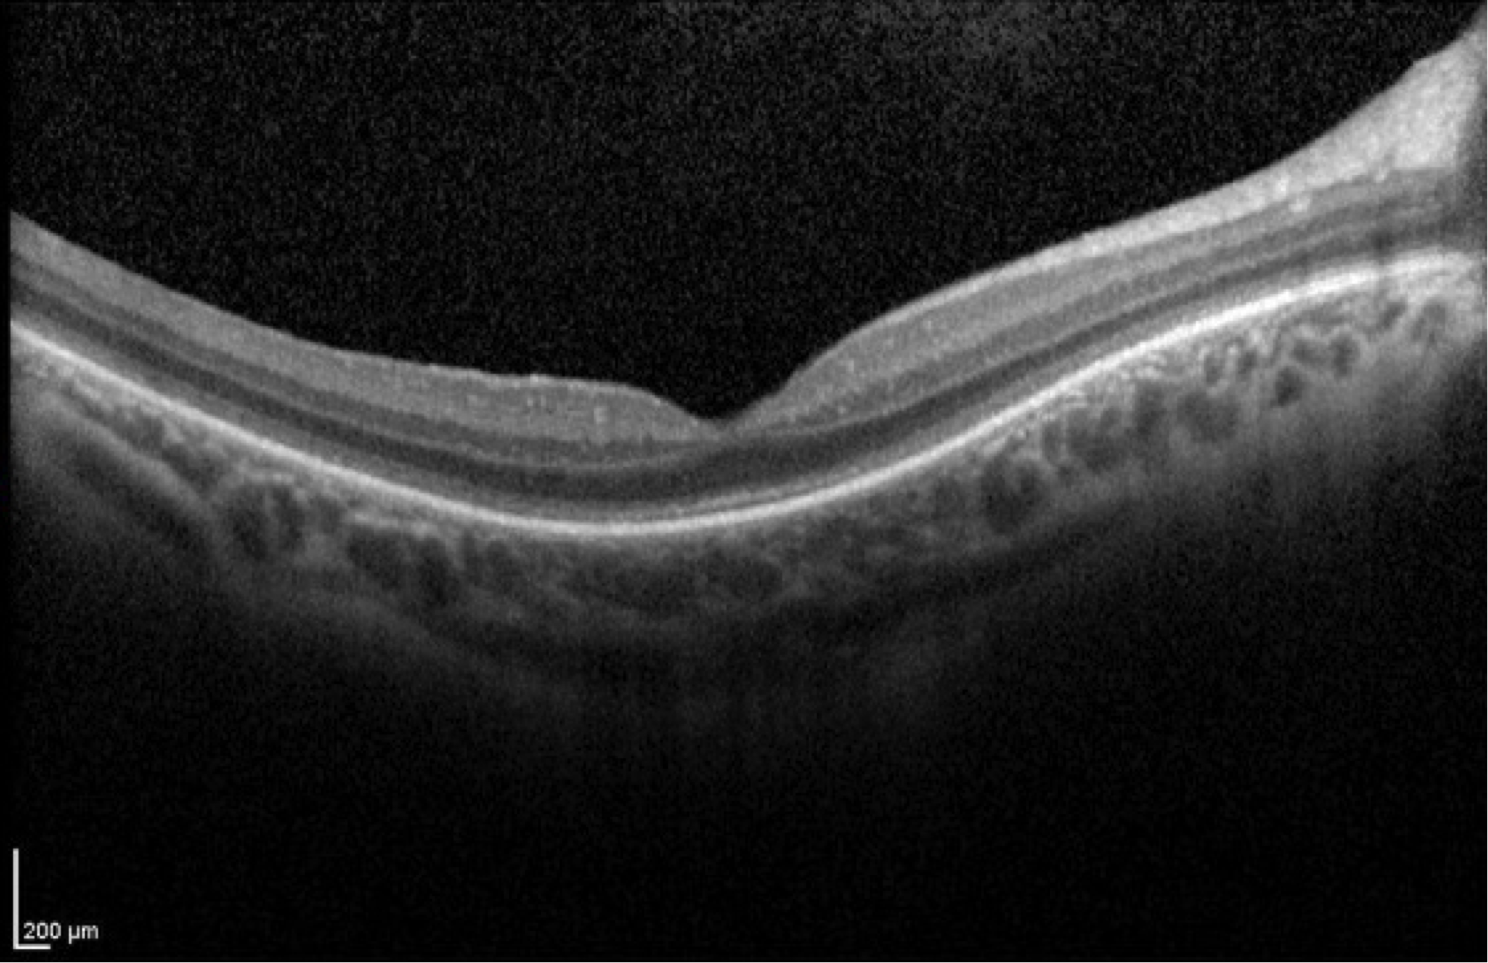

Case 15 is 5 years old and has 20/40 visual acuity. His normally sighted parents noticed that he bumped into things inexplicably shortly after he began to walk. They sought medical attention and he was given hyperopic spectacles of about 4 diopters which seemed to help with his central vision. However, his parents still suspected that his peripheral field was constricted because he would back up to find things. Electroretinography was then performed which revealed reduced scotopic responses and completely extinguished photopic responses. Goldmann perimetry revealed a V4e isopter about 50 degrees in diameter.

Optical coherence tomogram of the right eye.